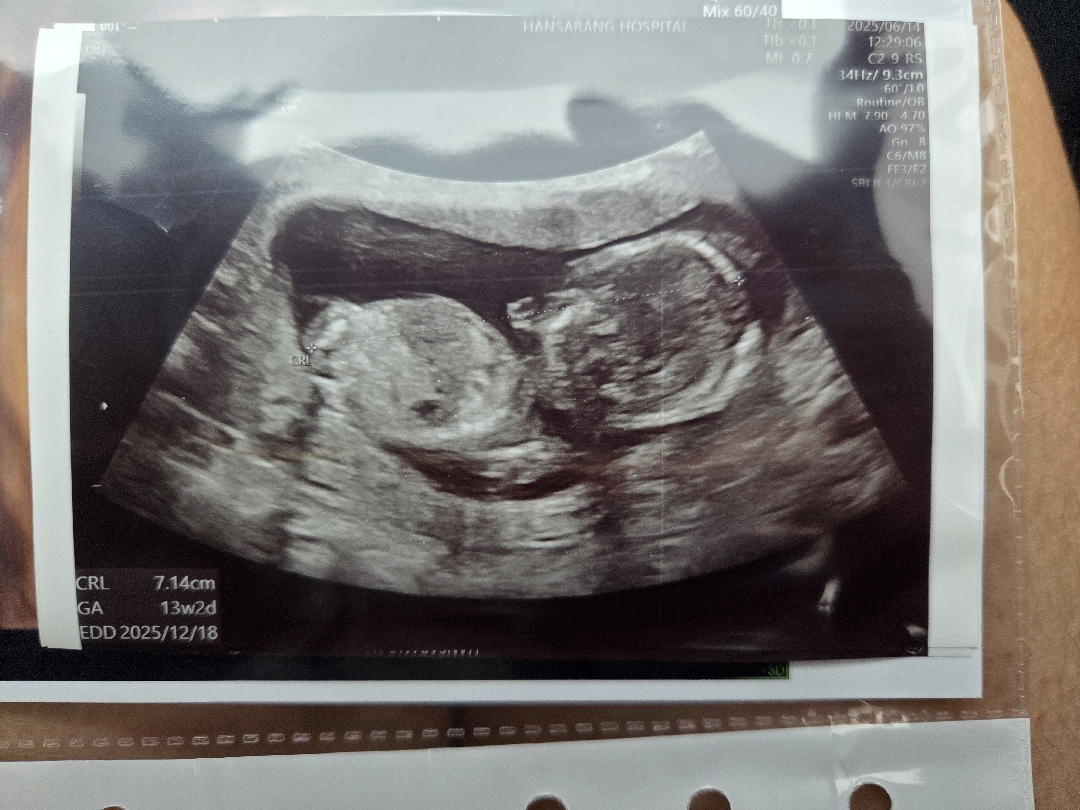

돌기가 안 보이는 사진이예요.

13주2일

아들일까요?딸일까요?ㅎㅎ 병원에서는 아무도말도 안해주시던데ㅠ